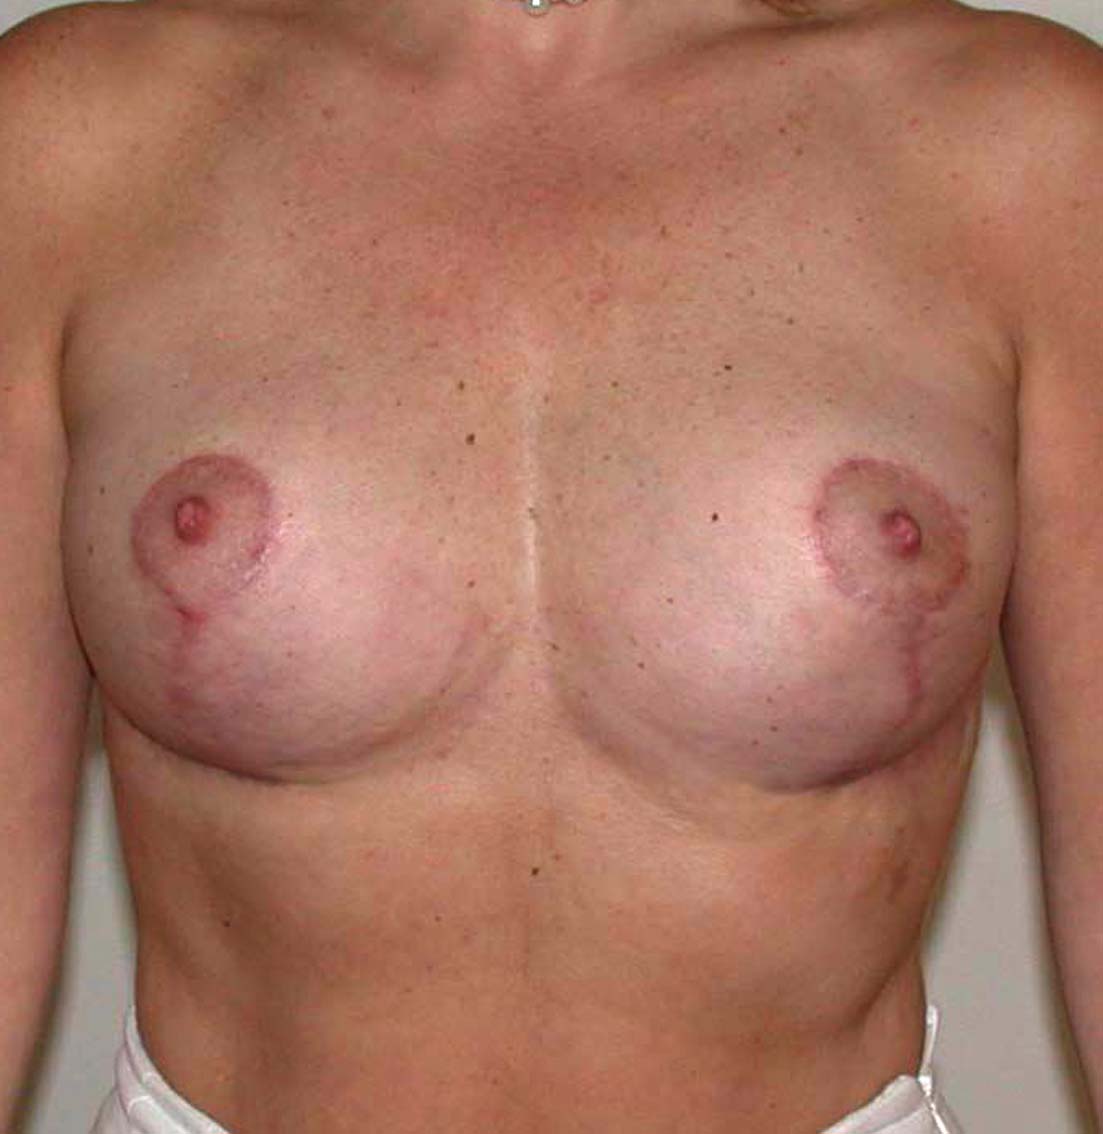

Cet album contient des exemples de plasties mammaires de correction de ptôse sans adjonction ou diminution de volume du sein. Seul le tissu mammaire présent est remodelé et repositionné. Le volume des seins est identique avant et après l’intervention.